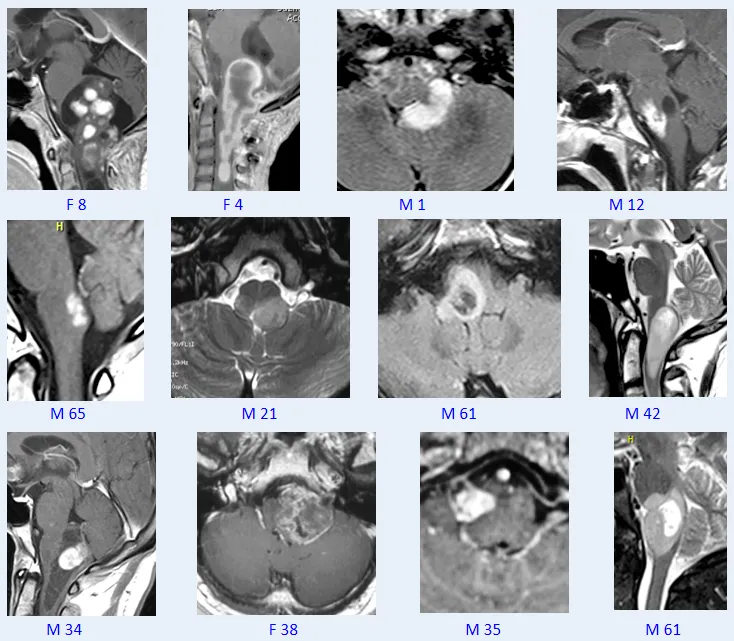

在第四届世界神外顾问团云端峰会时,巴教授就进行了主题为《Surgical treatment of brainstem glioma脑干胶质瘤的外科治疗》的精彩演讲。巴教授精选其206例脑干胶质瘤案例进行了详细的分享,其中大多数都是低级别的毛细胞型星形细胞瘤——脑干不是”无人之地“,对于低级别患者,尤其是毛细胞星形细胞瘤患者,我们甚至可以治愈他们,治愈意味着至少25年无肿瘤进展,而我已经治愈了其中的一些患者。点击阅读:1974-2024携手脑干50年的“love story”「INC云端峰会」巴教授精彩分享

▼巴教授脑干毛星50+例影像图汇

1.脑干不是“无人区”!

2.显微手术在局灶性脑干胶质瘤的整体管理中发挥着重要作用。

3.”低级别“胶质瘤是合适的手术候选者。

4.在许多情况下,可以尝试并实现治愈。

近40年,数千台疑难神经外科疾病手术,巴教授历经千万个小时用超精确的物理剥除诠释了医术为何为艺术。